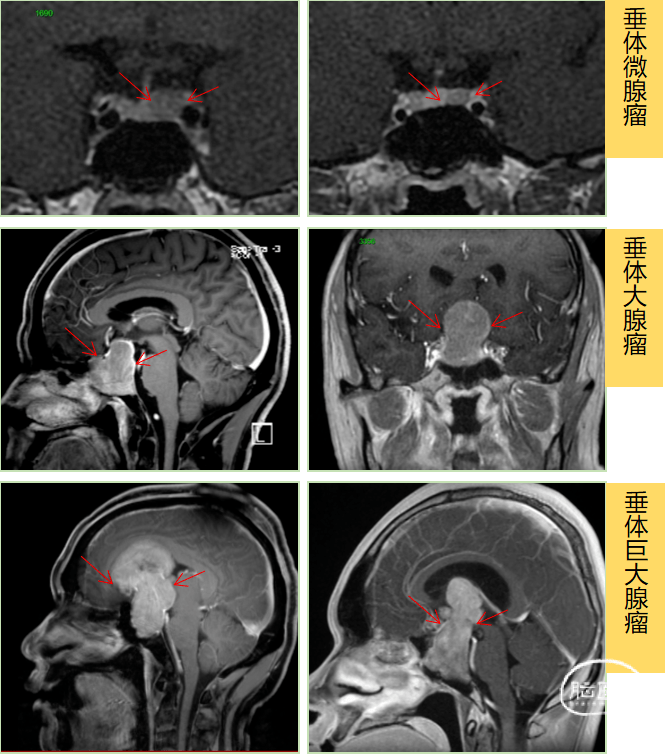

垂体瘤MRI

垂体腺瘤mri图

侵袭性垂体瘤的mri 征象

中年女性,视力下降2 年,巨大垂体瘤